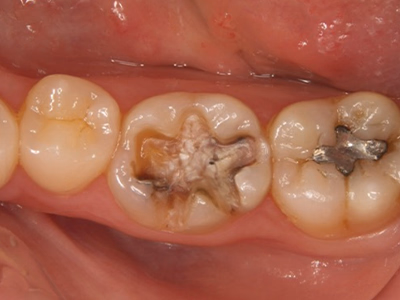

治療前後写真

治療前

治療後

年齢・性別

20歳・女性

来院理由

銀歯が取れてしみる

治療内容

ルーペ下でカリエス除去

精密印象採得→後日セラミックインレーを強力接着

メンテナンス移行

治療期間

1日(装着は後日)

費用

35,000円

リスク・副作用

再補綴時に歯髄損傷リスク上昇

残存歯質が少ない場合は破折の可能性

医院コメント

適合・耐久性・審美性を重視したセラミックで金属露出を解消。